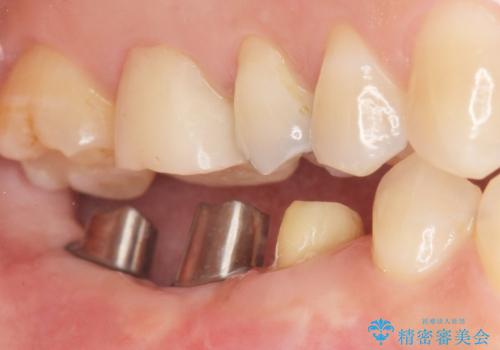

奥歯が割れている 抜歯してインプラントへ 40代女性

- 奥歯の痛みを主訴に来院された患者様です。

精査したところ、右下の奥歯(右下6)は割れており保存不可能な状態でした。

患者様のご希望により、右下大臼歯2本(右下76)のインプラント治療、右下小臼歯(右下5)の根管治療及び補綴治療を行いました。

割れていた歯の周囲組織の炎症が強く、骨の厚みが薄かったため、インプラント埋入時に骨増生(GBR)を行いました。